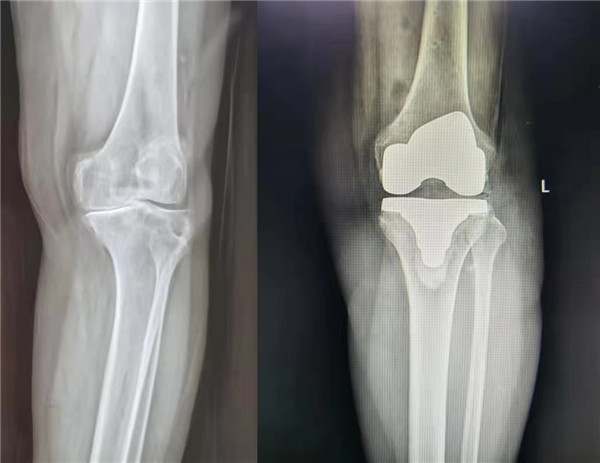

6月9日,由中华医学会骨科学分会候任主任委员、西安交通大学第二附属医院关节外科中心主任王坤正教授主刀,杨佩主任医师、王春生副主任医师、田润副研究员协助,成功完成了我国首例国产髋膝兼容关节手术机器人辅助全膝关节置换手术。

该手术使用的“ARTHROBOT”七轴髋膝兼容关节手术机器人,在术中可对膝关节活动度、下肢对线与关节间隙进行实时评估,依照术中实际情况实时调整规划方案,并按规划精准完成股骨与胫骨侧的截骨,误差控制在1mm与1˚范围以内,实现膝关节个性化、精准化手术治疗。

本次手术机器人“ARTHROBOT”,是国内首款由医生与工科团队基于临床刚性需求合作完成研发、具有完全自主知识产权的首款髋膝兼容七轴协作手术机器人,在第一阶段已完成百余例机器人辅助髋关节置换手术的基础上,突破多个技术难题,再次成功开展了机器人辅助全膝关节置换手术,在关节手术机器人领域成功打破了国外品牌的垄断局面。